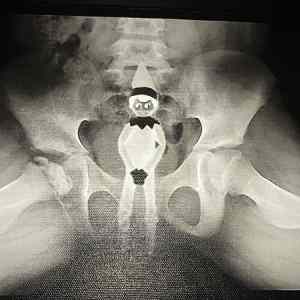

Obrázek The ELF

Malokdo by se sral s vyrobou elfa, aby na rentgenu vypadal tak dobre. Kovove zornicky, oboci ...

podle přítomnosti růstových chrupavek je zjevné, že se jedná o dítě, navíc vpravo je patrna osteomyelitida pravého kyčelního kloubu, tzv. morbus Legg-Calvé-Perthes, což je právě nemoc dětského věku... jako vedlejší nález ještě vidím cizí těleso v análním otvoru... cpt. out

No já myslím, že větší problém bude spíš porušený pánevní kruh, než ten elf v perdeli :-D :-D :-D

Major Zeman: Tam nejde o to že už ji tam má, ale že ji bude potřebovat. Má pravý kloub už dost sjetý, technickou by to neprošlo.

To neni endoproteza, to má větší kontrast a hřebík v kosti https://zdravi.euro.cz/denni-zpravy/z-domova/lepsi-kycle-budou-od-pristiho-roku-na-prodej-469367

Hlavne to vypada ha brzkou endoprotezu praveho kycelniho kloubu.